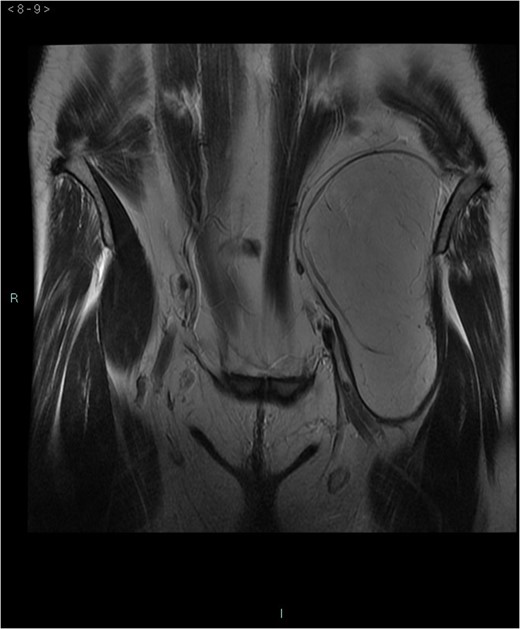

A 58-year-old woman was evaluated for lower abdominal pain, without additional symptoms. An abdominal ultrasonography revealed the presence of a 15 cm homogenous mass, located in the left pelvic cavity. Subsequent MRI showed a capsulated mass, isointense with the adipose tissue, longitudinally extending from the left inguinal area to the left leg root and located on the medial aspect of the left iliac bone. MRI also revealed within the mass some fibrotic branches containing small blood vessels. No evidence of extracapsular invasion of the surrounding structures was evident (Figs 1–6).

After multidisciplinary team discussion, surgical resection of the mass was planned: through a Pfannestiel incision a retroperitoneal dissection was performed, until exposition of the overmentioned mass, which was completely enucleated. During the operation, the absence of tumor infiltration of the surrounding structures was confirmed. No intraoperative histopathologic examination was carried out and the lesion was sent for definitive pathological examination. Macroscopically, the tumor presented as a well circumscribed encapsulated soft mass without infiltrative growth and/or satellite nodules. Tumor size was 15 × 7.5 × 6.5 cm3 and the weight was 309 g. External surface was smooth and the section had a lobulated aspect with a yellow-brown color. The histopathology examination revealed an adipocyte proliferation with moderate volume variation. Two populations of adipocytes were identified: one cluster with small, bland nuclei and the other with round to oval nuclei, with vacuolated eosinophil cytoplasm. In addition, rare multinucleated giant cells were observed. No cellular atypia was present. Immunohistochemistry was positive for S-100 and negative for MDM-2 (murine double-minute type 2) (Figs 7–9). Postoperative course was uneventful and the patient was discharged after 2 days.

Preoperative differential diagnosis is mainly based on radiologic imaging and is very difficult, because no pathognomonic signs exists for diagnosis of hibernoma; usually CT-scan shows an homogenous lesion, whose density is between subcutaneous fat and skeletal muscle; MRI shows slightly lower signal intensity on T1 weighted spin-echo (T1WSE), marked enhancement and partial fat suppression on short Tau inversion recovery (STIR) and fat-saturated sequences [5].